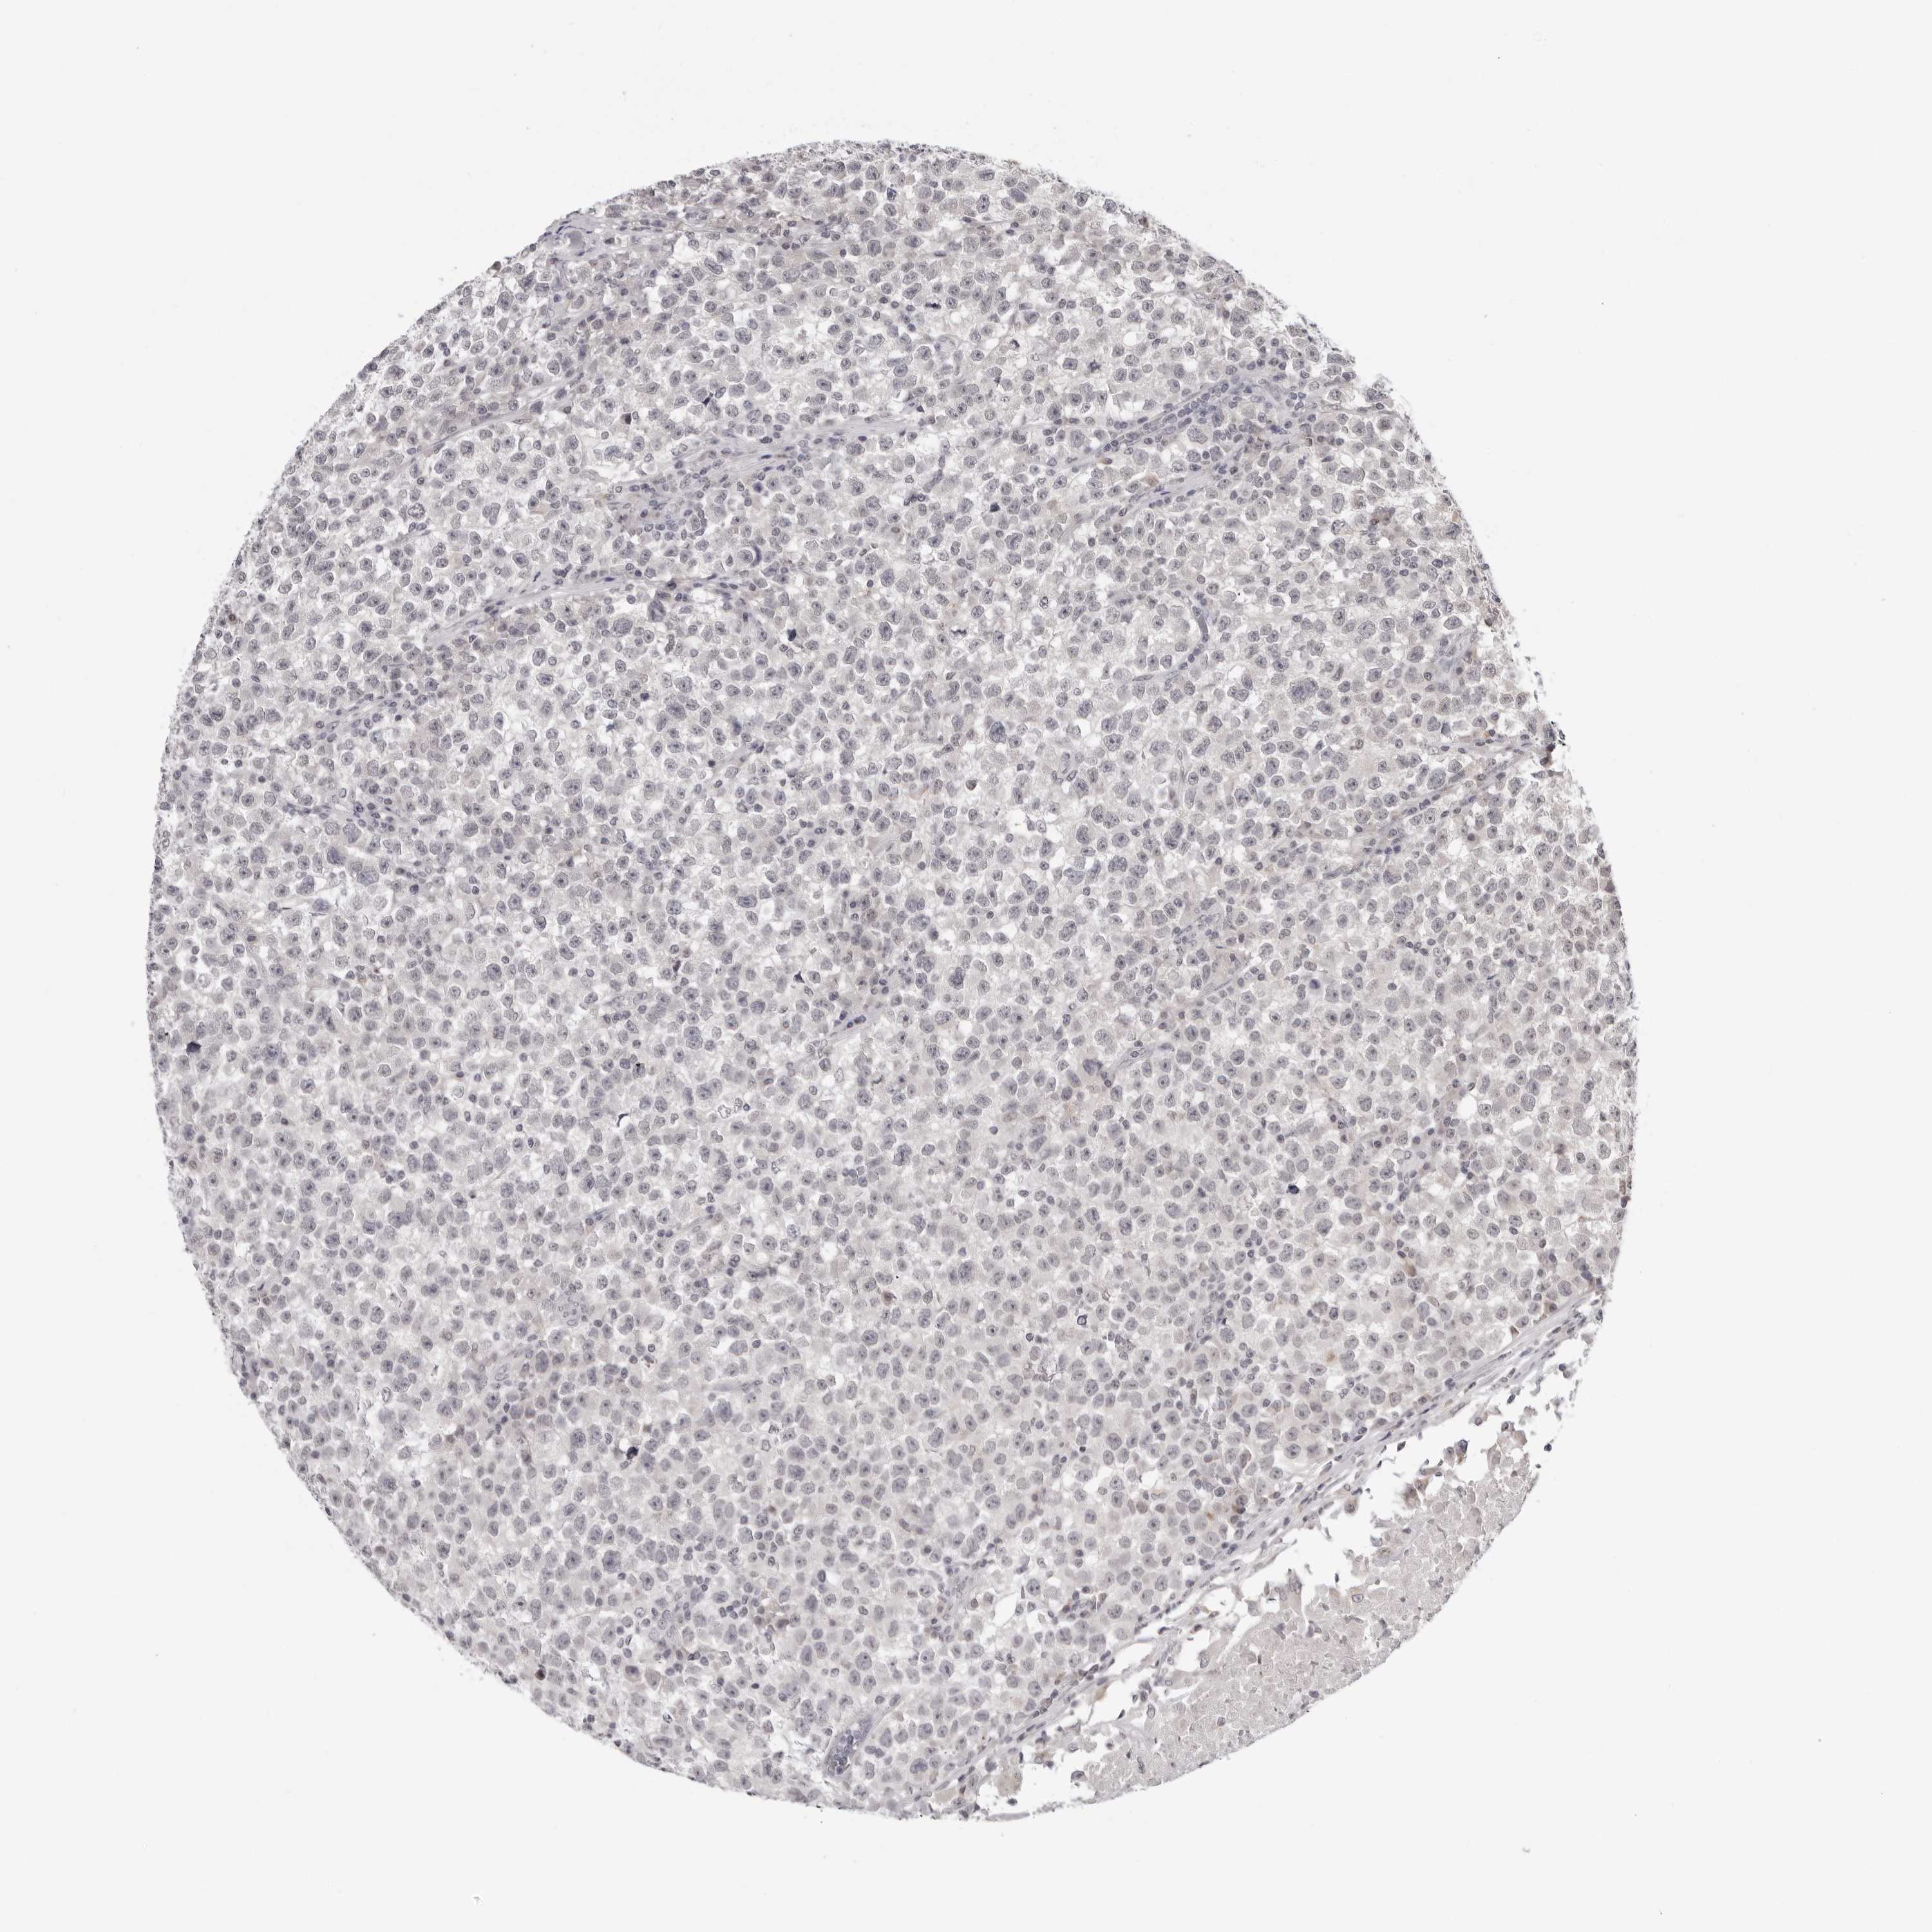

TESTIS CANCER - Protein expressioni

A mouse-over function shows sample information and annotation data. Click on an image to view it in a full screen mode. Samples can be filtered based on level of antibody staining by selecting one or several of the following categories: high, medium, low and not detected. The assay and annotation is described here.

Note that samples used for immunohistochemistry by the Human Protein Atlas do not correspond to samples in the TCGA dataset.

Antibody stainingi

Antibody staining in the annotated cell types in the current human tissue is reported as not detected, low, medium, or high, based on conventional immunohistochemistry profiling in selected tissues. This score is based on the combination of the staining intensity and fraction of stained cells.

Each image is clickable and will lead to virtual microscopy that enables deeper exploration of all samples and also displays staining intensity scores, fraction scores and subcellular localization as well as patient and tissue information for each sample.

Antibody HPA028411

Staining

High

Medium

Low

Not detected

Intensity

Strong

Moderate

Weak

Negative

Quantity

>75%

75%-25%

<25%

None

Location

Nuclear

Cytoplasmic/membranous

Cytoplasmic/membranous,nuclear

Carcinoma, Embryonal, NOS

Seminoma, NOS